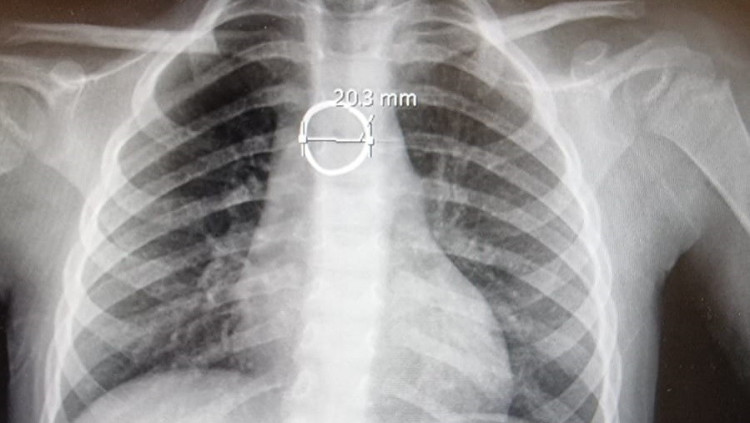

פעוטה מצפון הארץ בלעה טבעת ונאלצה לעבור ניתוח חירום - כך זה הסתיים